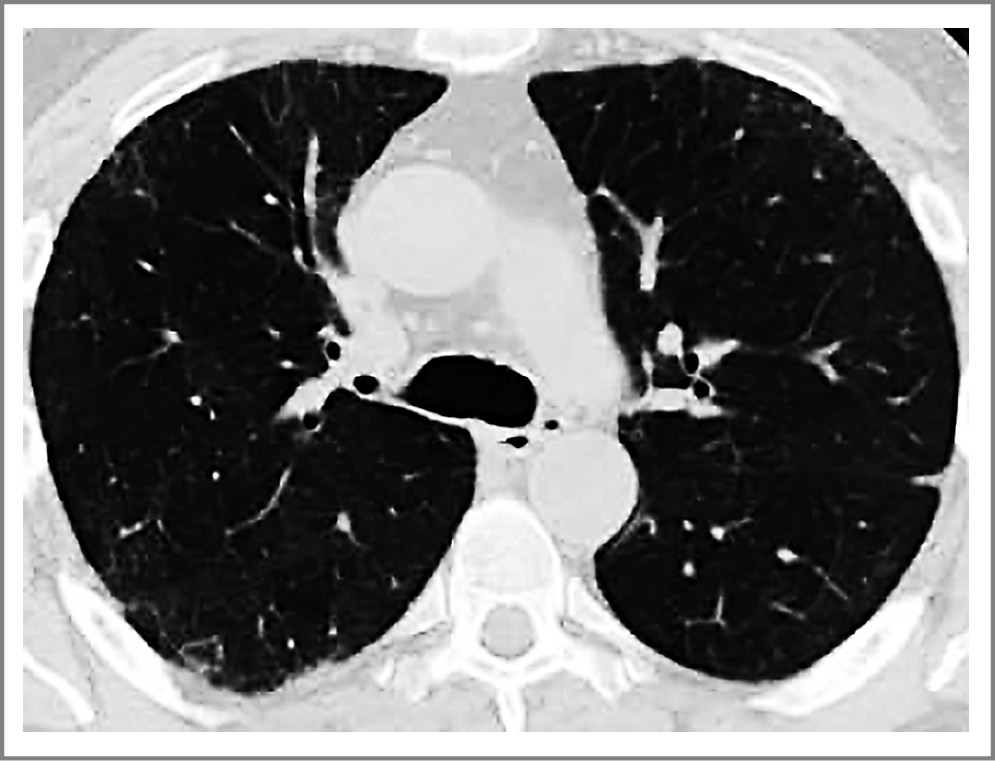

Одним из легочных проявлений пост-COVID-19 может быть развитие организующейся пневмонии (ОП) – варианта интерстициальной пневмонии [13]. Часто ОП манифестируют после перенесенных вирусных легочных инфекций. В частности, развитие ОП описано после SARS (Severe Acute Respiratory Syndrome – тяжелый острый респираторный синдром) и MERS (Middle East Respiratory Syndrome – ближневосточный респираторный синдром), вызываемых коронавирусами, родственными SARS-CoV-2 [14]. Другими причинами развития ОП могут быть нежелательные лекарственные реакции, системные заболевания соединительной ткани. Для ОП более характерно подострое начало; типичными симптомами заболевания являются лихорадка, малопродуктивный кашель, одышка, боли в грудной клетке. В тяжелых случаях развивается дыхательная недостаточность, требующая респираторной поддержки. При лабораторном обследовании часто выявляют значительное повышение уровня воспалительных маркеров – скорости оседания эрит- роцитов, С-реактивного белка (СРБ) и фибриногена [15]. Характерными компьютерно-томографическими признаками ОП является наличие субплевральных и перибронхиальных зон уплотнения легочной ткани по типу «матового стекла» и консолидации, симптомов «воздушной бронхографии» и «обратного гало» (рис. 1) [16]. Таким образом, клиническая и лабораторно-инструментальная картины заболевания у пациентов с коронавирусной пневмонией и ОП во многом сходныа, и дифференциальная диагностика данных состояний может оказаться затруднительной.

Рис. 1. Симптом «обратного гало» у пациента с ОП. / Fig. 1. Reverse halo symptom in a patient with organizing pneumonia.